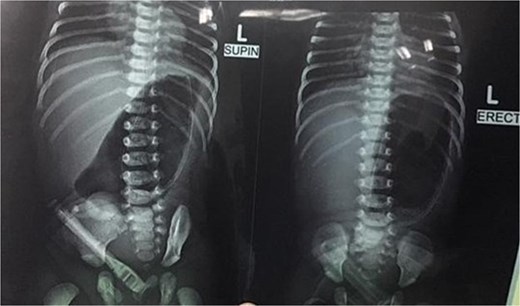

Initial management included nil per oral, fluid resuscitation, and nasogastric tube insertion. Laboratory investigations were unremarkable. Plain abdominal radiography revealed a single gastric air bubble with no distal gas, consistent with gastric outlet obstruction (Fig. 1). An upper gastrointestinal contrast study confirmed pyloric obstruction, with no contrast passing into the duodenum (Fig. 2).

Upper gastrointestinal contrast study demonstrating pyloric obstruction.

The diagnosis of PA is typically confirmed postnatally based on clinical presentation, radiographic findings, and intraoperative exploration. Non-bilious vomiting, abdominal distension, and failure to pass stool are common clinical features, as seen in our patient [8]. Plain abdominal radiography often reveals a single gastric air bubble with no distal gas, while contrast studies demonstrate failure of contrast to pass beyond the pylorus, as observed in our case [9]. These findings are consistent with gastric outlet obstruction, which is pathognomonic for PA.